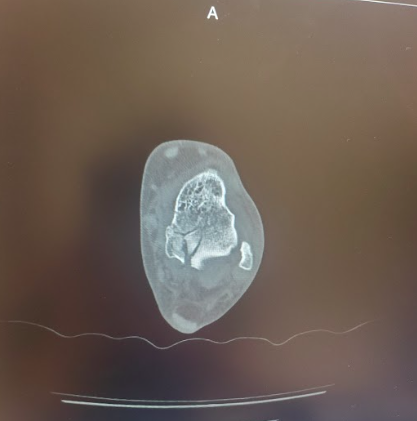

Talus Fracture

Post-op CT images